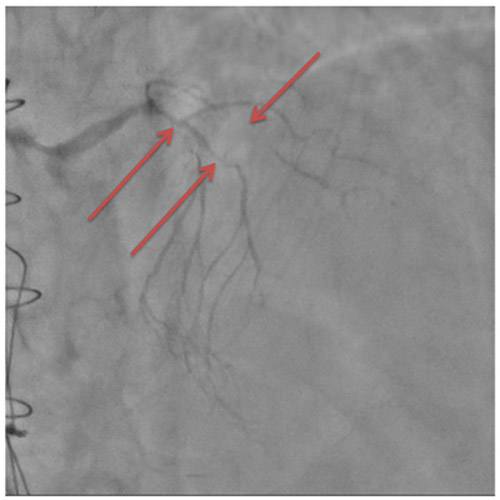

En effet, sur la coronarographie initiale, le réseau natif est quasi occlus, avec une subocclusion longue de l’IVA proximale donnant les premières branches septales, une occlusion chronique de la 2e diagonale, une occlusion chronique de la Cx proximale et de la CD ostiale.

Image 1 : Subocclusion de l’IVA proximale et moyenne (flèches du bas) et occlusion chronique de la 2e diagonale (flèche du haut)

Image 2 : occlusion chronique de la circonflexe proximale